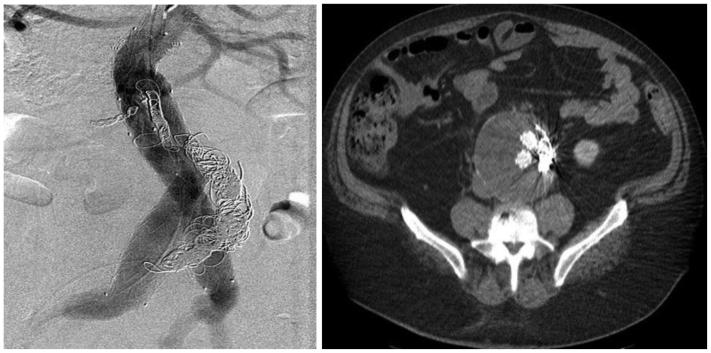

A primary aortocaval fistula (ACF) is a rare complication of abdominal aortic aneurysms caused by erosion of the aortic wall into the vena cava. It is more frequently observed in the setting of ruptured abdominal aortic aneurysms and presents a unique challenge for vascular surgeons. Both open and endovascular techniques exist, with the main differences being perioperative mortality and recurrence rates. We present a case of an ACF diagnosed intraoperatively, which persisted after endovascular aneurysm repair in conjunction with a type II endoleak. We applied a unique staged, triple endovascular approach to close the ACF via caval and aortic exclusion of inflow and outflow vessels.

原发性主动脉腔静脉瘘(ACF)是腹主动脉瘤的一种罕见并发症,由主动脉壁侵蚀进入腔静脉所致。在破裂性腹主动脉瘤中更常观察到,对血管外科医生构成独特挑战。开放手术和血管内技术都存在,主要区别在于围手术期死亡率和复发率。我们报告一例术中诊断为ACF的病例,该病例在血管内动脉瘤修复术后伴有II型内漏持续存在。我们采用了一种独特的分期、三重血管内方法,通过腔静脉和主动脉对流入和流出血管的封堵来闭合ACF。